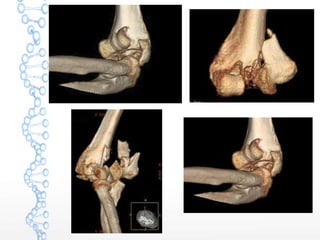

TERRIBLE TRIAD